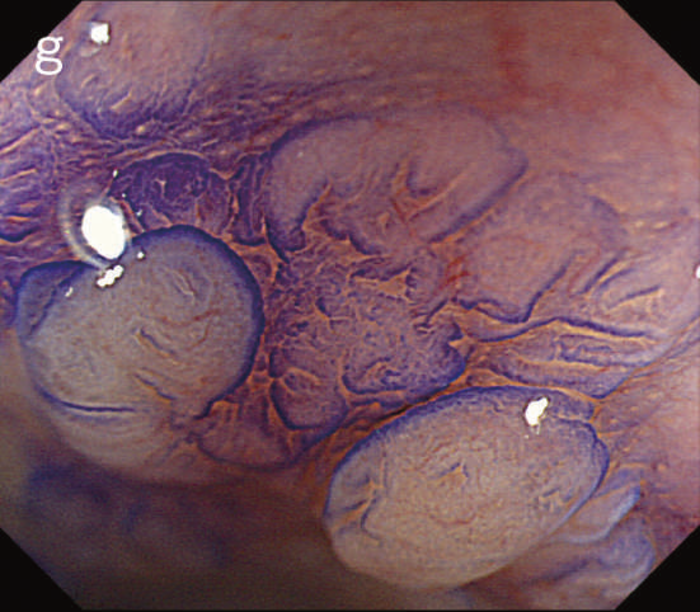

Non-polypoid lesionは規約における肉眼型ではParis 0-Ⅱa,0-Ⅱb,Ⅱcに相当する病変である。発育進展分類である顆粒型側方発育型腫瘍(LST-G)や非顆粒型LST(LST-NG)病変も含まれる(図12)。

図12 Non-polypoid lesionの内視鏡所見

- 白色光観察

- インジゴカルミン散布像:境界がより明瞭に認識できる。

- 酢酸インジゴカルミン混合液(AIM)散布像:病変全体と周辺粘膜とのコントラストが明瞭となる。

- NBI非拡大観察像:非拡大においても境界の認識は比較的容易となる。

- NIBI拡大観察像:病変中心部では拡張した血管を認める。

- クリスタルバイオレット染色拡大観察像:病変中央では大腸不動の拡張したpitを認める。gの病変辺縁ではpit構造の違いにより周辺粘膜と病変の境界が認識できる。